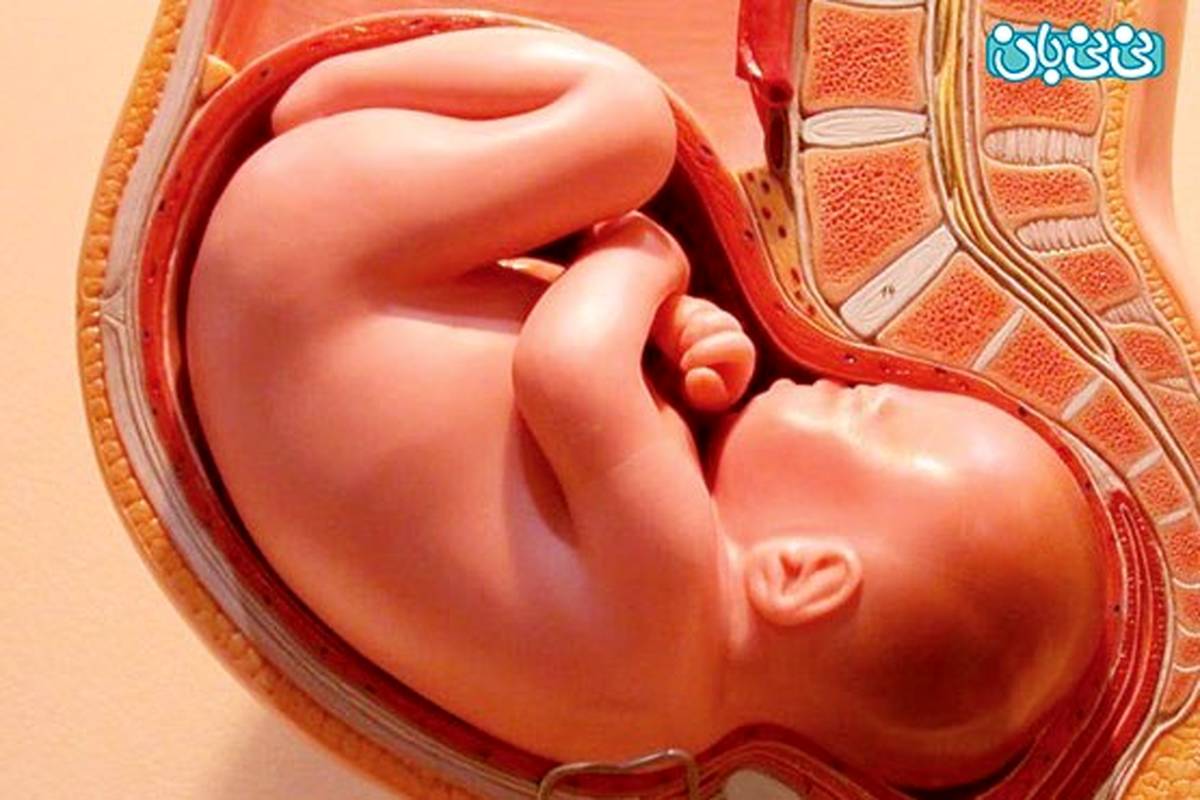

در ۹ هفته اول بارداری، بچه ی مادر، رویان نامیده می شود و پس از هفته دهم به جنین تغییر نام می دهد و در سونوگرافی او را به شکل یک دانه آماده رشد و شکوفایی می بینند.

معمولا با علایمی همچون حالت تهوع و عقب افتادگی قاعدگی، مادر متوجه بارداری خود می شود و آن را تا جنین کامل و تِرم حمل می کند اما مواقعی نیز هست که جنین ناگهان از رشد باز می ایستد و هیچ یک از این علایم خوب و خوشایند نیست. سراسر زندگی جنین در رحم مادر همراه با رشد و پیشرفت است و زمانی که این رشد متوقف می شود، شاید به این معنی باشد که بارداری ادامه نمی یابد.

محدودیت رشد درون رحمی (IUGR) به این معناست که اندازه جنین در رحم کمتر از انتظار است و این منجر به مشکلات بسیاری می شود. اگر جنین رشد کمتر از ۱۰ درصد سن بارداری داشته باشد احتمالا IUGR تشخیص داده می شود.

بچه با مایع آمنیوتیک در اطرافش محصور شده است بنابراین اگر آب یا مایع زیادی از بدن به یکباره خارج شد شاید نشانه این باشد که این کیسه دچار پارگی شده است. این وضعیتی است که مادران در پایان بارداری منتظر آن هستند و اگر این اتفاق زودتر بیفتد باید بچه از رحم خارج گردد.

12- عدم حرکت جنین

درست است که جنین در سه ماهه اول رشد و حرکت دارد ولی مادر معمولا آنها را تا سه ماهه دوم بارداری احساس نمی کند. داشتن احساس لگد زدن و حرکت بچه در شکم احساسی است که مادر از سلامتی جنین خود مطمئن می گردد.

اگر حرکات بچه در سه ماهه سوم قطع شد مادر باید گوش به زنگ باشد و سریعا به پزشک مراجعه نماید. یک دسته دلایل متفاوتی برای عدم حرکت بچه وجود دارد اما یکی از آنها مرگ جنین می تواند باشد.